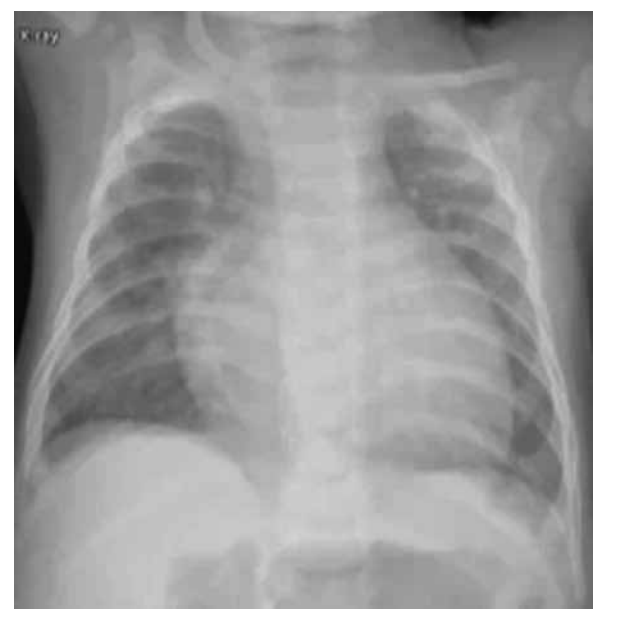

Uma lactente de 5 meses, do sexo feminino, foi internada na UTI com uma hipótese diagnóstica de choque séptico.

Apresenta síndrome de Down e defeito do septo atrioventricular com moderada repercussão. Está em uso de carvedilol,

captopril e furosemida. Aguarda agendamento cirúrgico para correção total da cardiopatia. Vem apresentando febre, há

três dias, de até 38 ºC. Realizou-se raio-X do tórax (figura a seguir), administrou-se a primeira dose de ceftriaxona, e a

paciente foi encaminhada para a UTI.

(Arquivo pessoal; imagem usada com autorização)

Ao exame físico, encontra-se sonolenta, mas abre os olhos ao chamado. Frequência respiratória: 65; batimento de aleta nasal; retração intercostal e subdiafragmática; saturação de 91% com máscara não reinalante 15 L/minuto; FC: 175; tempo de enchimento capilar de 5 segundos; pressão arterial: 75 x 55. Ausculta cardíaca: bulhas rítmicas normofonéticas com sopro sistólico +++. Ausculta pulmonar: murmúrio vesicular presente bilateralmente com estertoração crepitante bilateral nas bases. Abdome: globoso, flácido, doloroso à palpação do hipocôndrio direito, com fígado palpável a 4 cm do rebordo costal direito.

Com relação à hipótese diagnóstica e à conduta adequada, é correto afirmar que se trata de choque